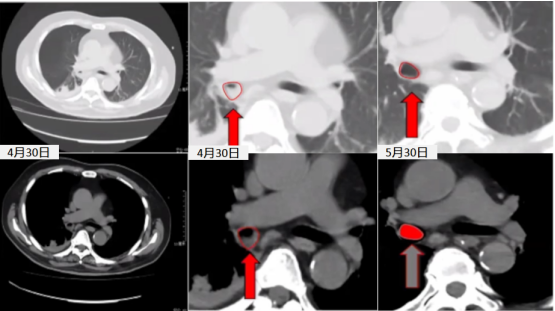

病例2:患者,男性,71岁。主诉“双下肢麻木、力弱4月余,再发1月”。诊断:慢性炎性脱髓鞘性多神经根神经病。4月23-26日予甲强龙1.0 g冲击治疗,患者自觉症状明显缓解。4月26日予甲强龙0.5 g治疗,2天后喘憋加重,出现Ⅱ型呼吸衰竭。4月28日转入ICU,深吸气量为450~500 ml,给予NPPV治疗,1天后气管插管,可吸出大量痰液。4月30日,胸部CT提示右肺中间支气管痰栓形成。4月30日CT:纵隔窗无明显异常,但在肺窗可见右下支气管痰栓堵塞。治疗好转后复查胸部CT(5月30日)发现痰栓消失(图2)。该患者的气道问题主要包括:口干、鼻干;痰液黏稠、不易咳出;痰栓、痰痂形成;气道阻力增加;胃胀气,肺通气量下降。

图2  患者胸部CT